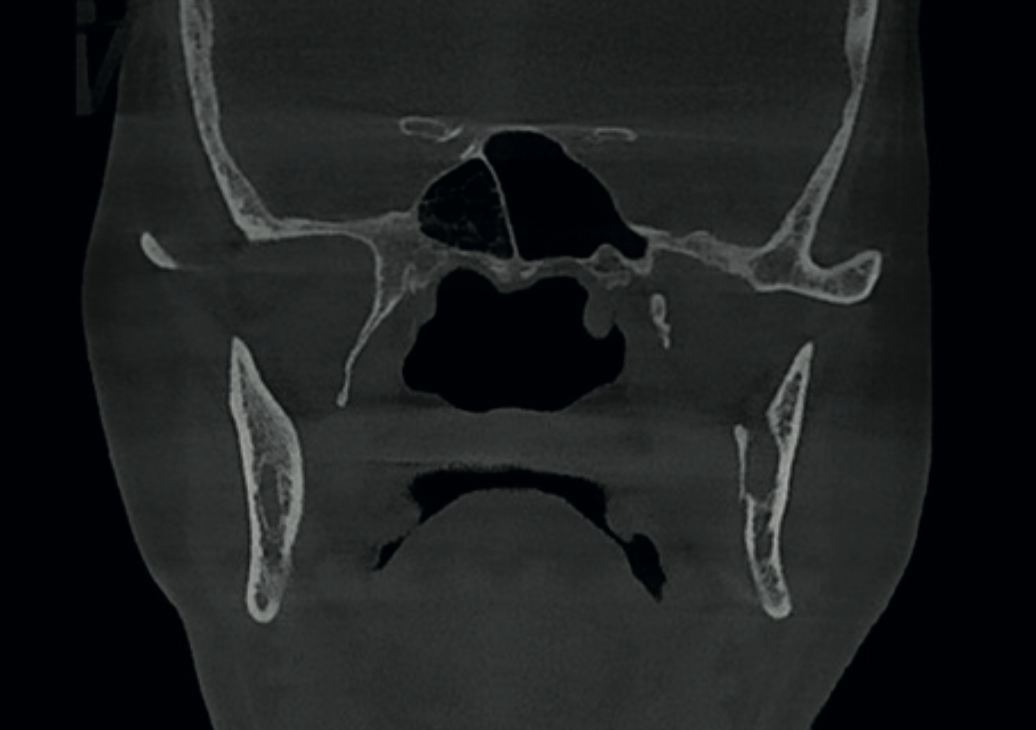

Coronal CBCT view showing streaks in the right compartment of the sphenoid sinus

Finding 2

Sphenoid sinus mucosal thickening

Streaks visible in the right compartment of the sphenoid sinus, consistent with thick mucus retention. Requires monitoring.